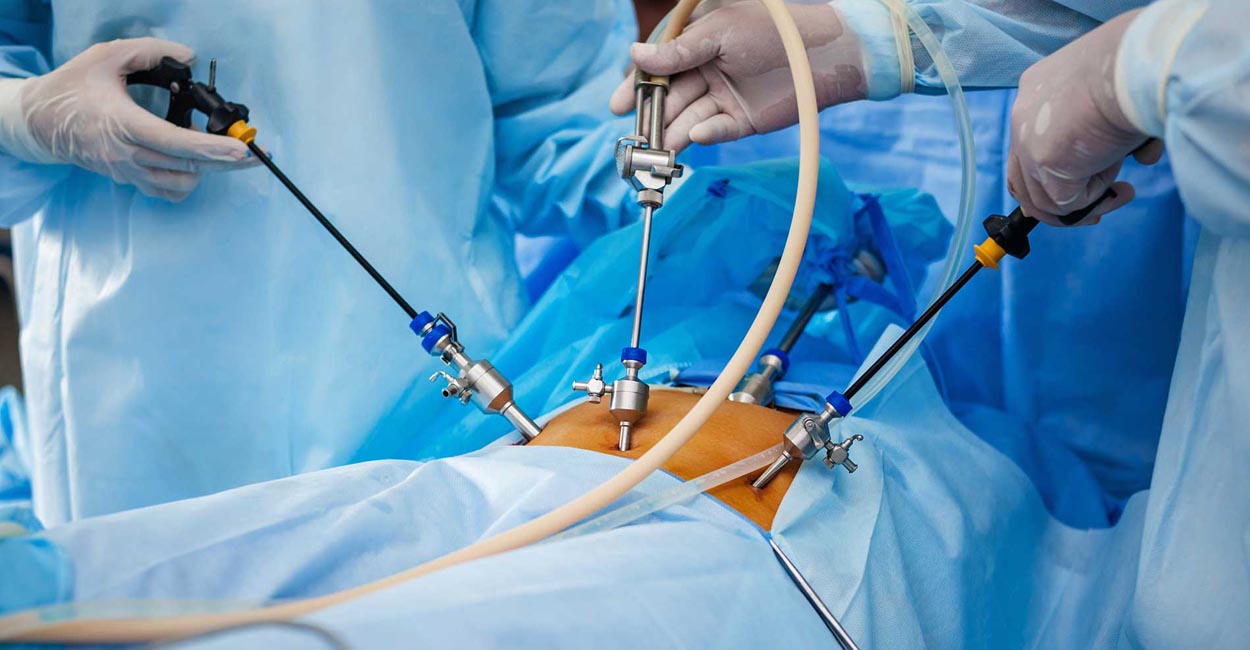

Laparoscopic surgery has transformed the way surgeries are performed. With shorter hospital stays, reduced complications, and faster recovery and mobility, laparoscopic surgery is now the preferred approach for surgical patients.

Laparoscopic surgery has become an essential component of modern surgical practice. Successful outcomes depend not only on the surgeon’s exceptional skills but also on utilizing the right instruments. We utilize advanced 4K laparoscopic systems to enhance precision and visibility during procedures.

Our facility features a state-of-the-art modular laparoscopic operation theater, equipped with advanced instruments and a team of trained professionals.